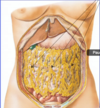

Label A and B:

- A = transverse mesocolon

- B = greater omentum